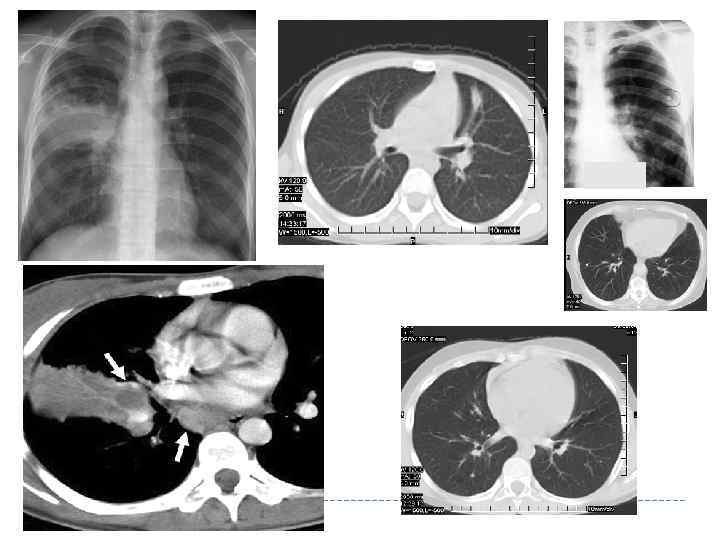

ПЕРВИЧНЫЙ ТУБЕРКУЛЕЗНЫЙ КОМПЛЕКС Характеризуется наличием очага или фокуса в легком, лимфангиита и поражением регионарных внутригрудных лимфатических узлов. Первичному туберкулезному комплексу соответствует «синдром биполярного тенеобразования» .

ПЕРВИЧНЫЙ ТУБЕРКУЛЕЗНЫЙ КОМПЛЕКС Характеризуется наличием очага или фокуса в легком, лимфангиита и поражением регионарных внутригрудных лимфатических узлов. Первичному туберкулезному комплексу соответствует «синдром биполярного тенеобразования» .

Рентгенологическая характеристика ПТК Стадии рентгенологических изменений ПТК: I. Стадия инфильтрации II. Стадия «биполярности» III. Стадия уплотнения IV. Стадия петрификации

Рентгенологическая характеристика ПТК Стадии рентгенологических изменений ПТК: I. Стадия инфильтрации II. Стадия «биполярности» III. Стадия уплотнения IV. Стадия петрификации

Рентгенологические признаки стадии инфильтрации ПТК Очаг или фокусное образование неправильной формы, с размытыми контурами и неоднородной структурой. Центральная часть затемнения, обусловленная первичным лёгочным поражением, имеет на рентгенограмме большую интенсивность, а окружающая перифокальная инфильтрация - меньшую. На стороне поражения отмечается также расширением и деформацией тени корня лёгкого с размытой наружной границей.

Рентгенологические признаки стадии инфильтрации ПТК Очаг или фокусное образование неправильной формы, с размытыми контурами и неоднородной структурой. Центральная часть затемнения, обусловленная первичным лёгочным поражением, имеет на рентгенограмме большую интенсивность, а окружающая перифокальная инфильтрация - меньшую. На стороне поражения отмечается также расширением и деформацией тени корня лёгкого с размытой наружной границей.

I. Стадия инфильтрации ПТК Характеризуется наличием одиночной гомогенной тени сливающееся с расширенным корнем легкого 13

I. Стадия инфильтрации ПТК Характеризуется наличием одиночной гомогенной тени сливающееся с расширенным корнем легкого 13

II. Стадия «биполярности» (рассасывания) Симптом Редекера – первичный аффект и измененные ВГЛУ Рассасывается перифокальное воспаление, исчезновение лимфангита

II. Стадия «биполярности» (рассасывания) Симптом Редекера – первичный аффект и измененные ВГЛУ Рассасывается перифокальное воспаление, исчезновение лимфангита

III. Стадия уплотнения ПТК Уплотнения фокуса Уплотнение фокуса 15 Появляется неоднородность фокуса за счет кальцинации

III. Стадия уплотнения ПТК Уплотнения фокуса Уплотнение фокуса 15 Появляется неоднородность фокуса за счет кальцинации

Рентгенологические признаки в стадию рассасывания и уплотнения ПТК постепенное исчезновение перифокальной инфильтрации в лёгочной ткани и перинодулярной инфильтрации в области корня лёгкого лёгочный компонент обычно представлен ограниченным затемнением или фокусом средней интенсивности, лимфатические узлы — расширением и деформацией корня лёгкого. размеры лёгочного компонента и поражённого корня лёгкого продолжают уменьшаться; постепенно в них обнаруживают признаки кальцинации 16

Рентгенологические признаки в стадию рассасывания и уплотнения ПТК постепенное исчезновение перифокальной инфильтрации в лёгочной ткани и перинодулярной инфильтрации в области корня лёгкого лёгочный компонент обычно представлен ограниченным затемнением или фокусом средней интенсивности, лимфатические узлы — расширением и деформацией корня лёгкого. размеры лёгочного компонента и поражённого корня лёгкого продолжают уменьшаться; постепенно в них обнаруживают признаки кальцинации 16

IV. Стадия петрификации ПТК 17 Интенсивная тень с четкими контурами (очаг Гона)

IV. Стадия петрификации ПТК 17 Интенсивная тень с четкими контурами (очаг Гона)

Стадия кальцинации очагов при ПТК характерно формирование в лёгочной ткани высокоинтенсивной очаговой тени с четкими контурами (очаг Гона) и включениями высокой плотности (кальцинатов) в регионарных лимфатических узлах 18

Стадия кальцинации очагов при ПТК характерно формирование в лёгочной ткани высокоинтенсивной очаговой тени с четкими контурами (очаг Гона) и включениями высокой плотности (кальцинатов) в регионарных лимфатических узлах 18